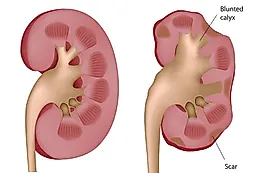

Во многих исследованиях выявлено, что патогенез таких камней приводит к прогрессированию обструкции, присоединению инфекции и потере функции почек.

Таким образом, наличие такого камня само по себе является показанием к вмешательству, даже если при этом нет симптомов